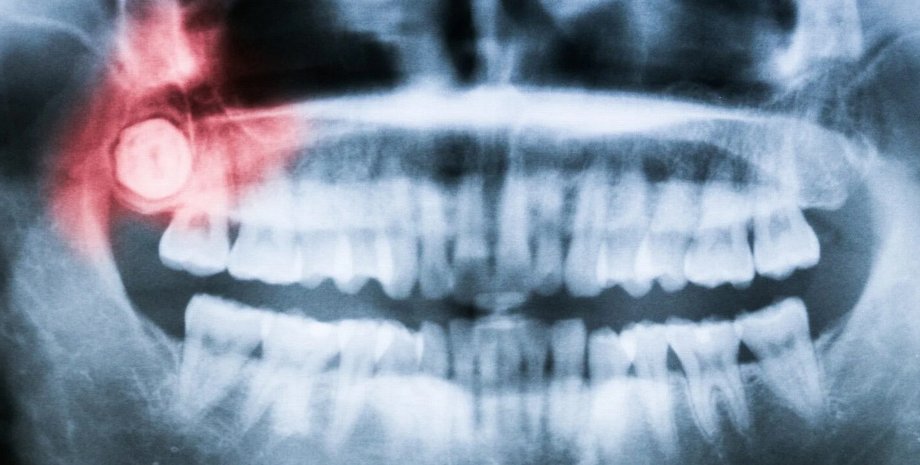

Ученые выяснили, почему у людей растут зубы мудрости во взрослом возрасте

Зубы, челюсть, рентген

Фото: popsci.com